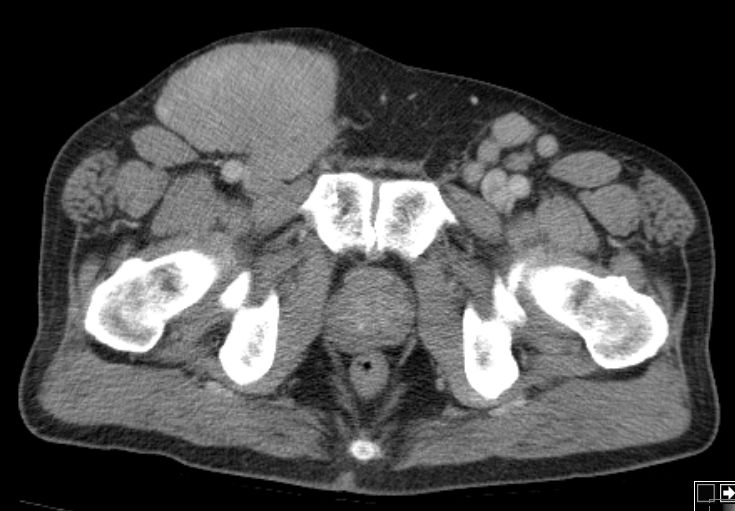

inguinaler Bulk |

72-jähriger Mann mit Verdacht auf

Hernia inguinalis rechts. PE: diffuses großzelliges B-Zellymphom.![]() |